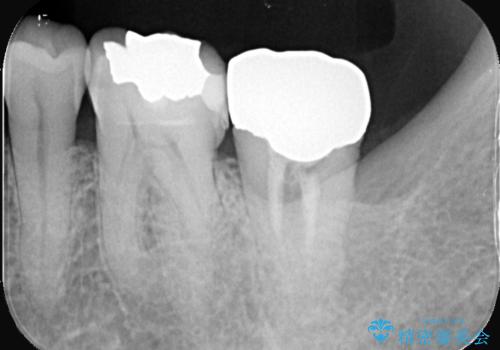

検査の結果、左下7番は歯周ポケットが8mmと深く、レントゲンでも根尖部から骨が溶けている状態が確認されました。エンドペリオ病変と診断し、精密根管治療による保存か、抜歯をしてインプラントで治療するかをご提案したところ、患者様は抜歯・インプラント治療を希望されました。